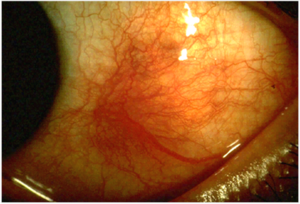

التهاب الصلبة (إنگليزية: Scleritis)، هو is a serious inflammatory disease that affects the white outer coating of the eye, known as the sclera. The disease is often contracted through association with other diseases of the body, such as granulomatosis with polyangiitis or rheumatoid arthritis. There are three types of scleritis: diffuse scleritis (the most common), nodular scleritis, and necrotizing scleritis (the most severe). Scleritis may be the first symptom of onset of connective tissue disease.[1]

- Redness of the sclera and conjunctiva, sometimes changing to a purple hue

The pain of episcleritis is less severe than in scleritis.[4] In hyperemia, there is a visible increase in the blood flow to the sclera (hyperaemia), which accounts for the redness of the eye. Unlike in conjunctivitis, this redness will not move with gentle pressure to the conjunctiva.

Scleritis is best detected by examining the sclera in daylight; retracting the lids helps determine the extent of involvement. Other aspects of the eye exam (i.e. visual acuity testing, slit lamp examination, etc.) may be normal. Scleritis may be differentiated from episcleritis by using phenylephrine or neosynephrine eye drops, which causes blanching of the blood vessels in episcleritis, but not in scleritis.[4]